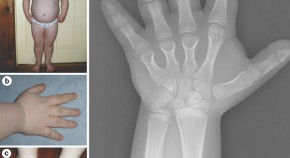

• This article presents the case of a child with pseudohypoparathyroidism type 1a and associated endocrinopathies, namely, growth hormone deficiency, hypothyroidism, parathyroid hormone resistance and insulin resistance. The article details the natural history and management of these endocrinopathies, including the controversy over growth-hormone therapy, and potential mechanisms for insulin resistance in pseudohypoparathyroidism type 1a.

• Benjamin U. Nwosu

• Mary M. Lee